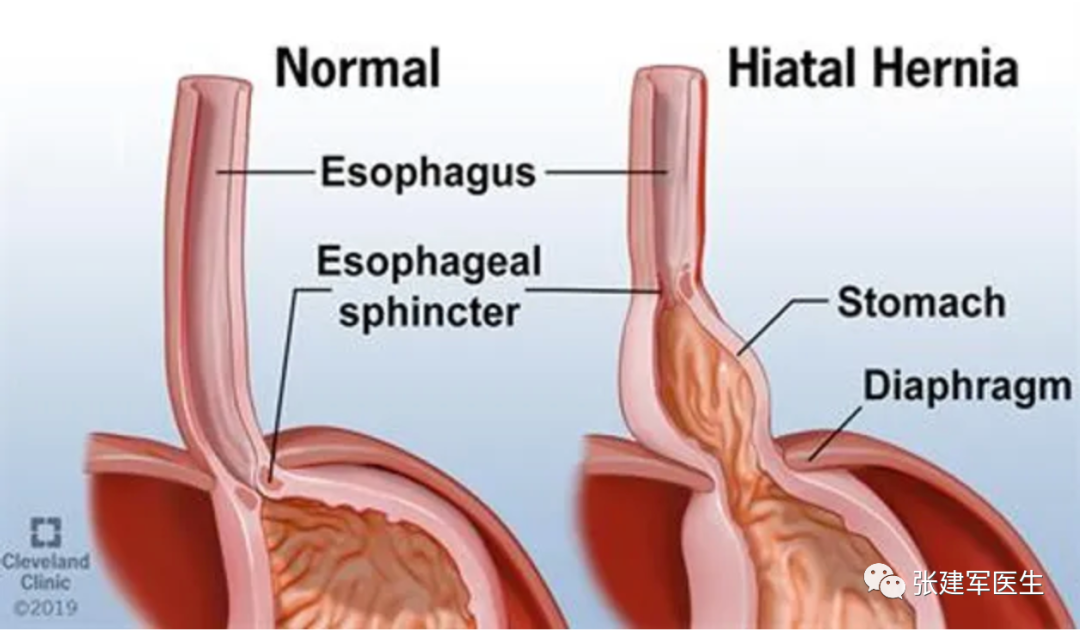

食管裂孔(Hiatus)是膈肌上的一个孔隙,食管通过该孔从胸部进入腹部。当胃的一部分通过膈食管裂孔进入胸腔,就发生食管裂孔疝(Hiatus herni),又称膈肌食管裂孔疝,简称裂孔疝。可导致胃食管返流或咽喉反流,其症状包括口腔酸味或胃灼热感。其他症状包括吞咽困难和胸痛。并发症可能包括缺铁性贫血,肠扭结或肠梗阻等。

Ⅰ型(滑动性食管裂孔疝):食管胃交界处(食管胃结合部)从腹部移位至胸部,约占 食管裂孔疝95% 的病例。